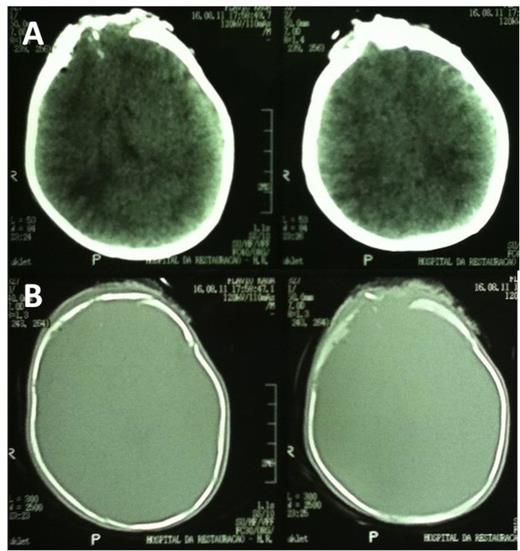

A computed tomography (CT) scan upon admission revealed a depressed skull fracture with an underlying frontal cerebral contusion and intraparenchymal bone fragments (Fig. 2).

Initial CT scan showing frontal contusion (A) and bone window images revealing frontal skull fracture (B).